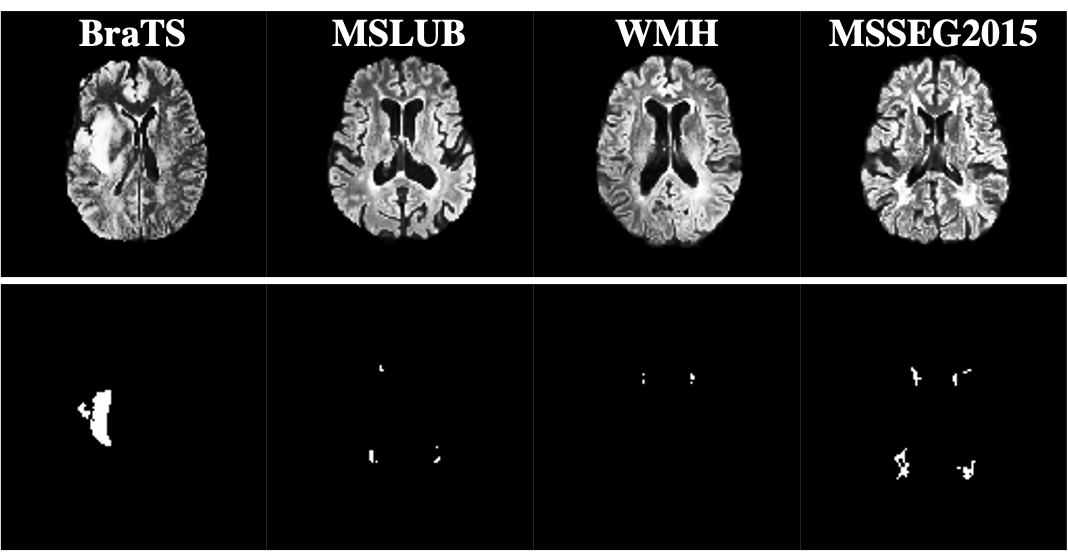

Our pre-processing pipeline closely follows Baur et al. [4]. First, we skull strip the FLAIR scans using ROBEX [14]. Subsequently, we register them to the SRI space [21]. Specifically, since [21] does not contain a FLAIR Atlas, we register the T1-weighted images of all data sets and apply the same transformation to the FLAIR images and the ground truth segmentation masks. This is possible, as T1- and FLAIR images and the segmentation files are co-registered in all the data sets used. Performing registration before skull stripping resulted in failed registrations in early experiments. The registration step is not vital for our algorithm but was purely done to ensure comparability with other methods. Figure 2 shows samples of pre-processed images from all four data sets.

To evaluate brain tumor detection, we use the training set of the 2020 version of the Multimodal Brain Tumor Image Segmentation Benchmark (BraTS) [18, 2, 3]. It contains T1, T2, and FLAIR scans of 371 subjects acquired across 19 institutions with multimodal, 3 Tesla MRI scanners. It also contains manual segmentations of the tumor regions by up to four raters. The BraTS images are already skull stripped. The MSLUB [16] data set consists of T1, T2, and FLAIR images of 30 subjects with multiple sclerosis (MS). They have been acquired at the University Medical Center Ljubljana (UMCL) with a 3 Tesla Siemens Magnetom Trio MR system. The consensus of three experts on white matter lesion segmentation is also included. As in [20], we evaluate on the White Matter Hyperintensities Segmentation Challenge (WMH) [15]. For this data set, T1 and FLAIR scans of 60 patients were acquired at three different sites in the Netherlands and Singapore. The sites used 3 Tesla MRI scanners from Philips, Siemens, and GE. Manual segmentation of the lesions was conducted by an expert radiologist. Lastly, we use the training data of the 2015 Longitudinal MS Lesion Segmentation Challenge [10]. This dataset has 21 T1, T2, PD, and FLAIR weighted MRI scans from 5 subjects recorded at the John Hopkins MS Center with a 3 Tesla Philips scanner. Manual lesion segmentations are available from two raters. We use the ratings of rater one (as indicated by the filename ”mask1.nii”) for our evaluation.

Tumors are usually much larger anomalies than MS lesions. We evaluated the exact distribution of anomaly sizes by performing a 3D connected component analysis on the segmentation maps of all data sets (table 1). MSLUB has the smallest anomalies and also the largest number of anomalies per scan.